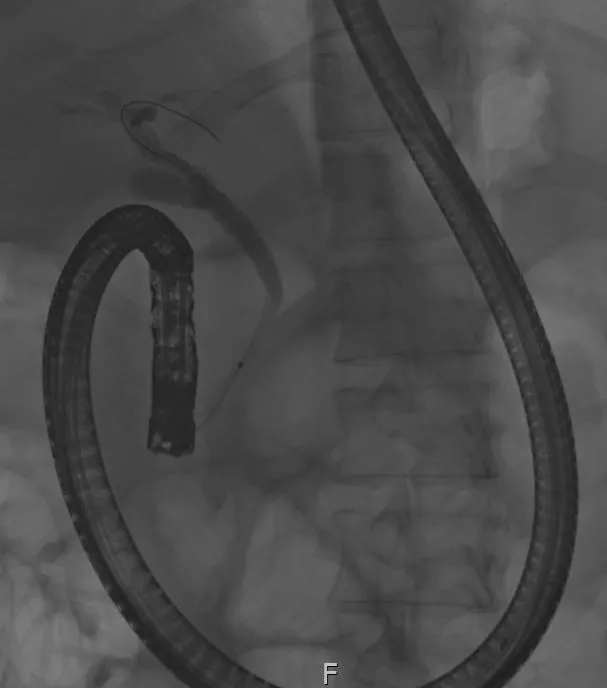

다음 날 ERCP를 시행하였고, 췌장의 괴사로 인해 십이지장 벽이 부어있었고, 십이지장으로의 내시경 통과가 쉽지 않았다. 정상적으로 십이지 장경(ERCP를 위한 내시경을 말한다.) 은 십이지장 2부에서 단축이 가능하나, 이분은 불가능하였다. 단축이 되면 내시경으로 인한 통증이 경감되나, 단축이 되지 않는 경우 내시경이 위 내에서 위를 계속 밀게 되어 시술이 매우 어렵고 환자도 통증을 심하게 호소한다. 진정 내시경(환자들이 흔히 수면 내시경이라고 불리는 말이다.) 이어도 통증은 느낄 수 있다.

내시경 단축이 되지 않은 모습. 이경우 환자의 통증이 심해 계속 움직여 시술 난이도는 올라간다.

췌장 주변의 괴사로 인해 십이지장이 부어 있다.